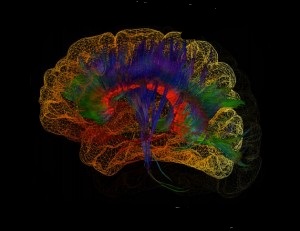

Brain Connectivity

To characterize the underlying architectures of brain networks is central to current neuroimaging research. Mathematical modeling provides generalizable definitions for the structural and functional organization of the human brain.